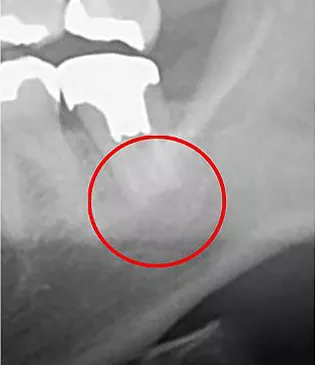

赤丸部分が問題の個所になりますが、一般的なレントゲンではしっかりと確認することは出来ませんが、

治療をする上で、最初の診査診断が非常に重要となります。

なぜなら、最初の段階で正確な診断を下さなければ、誤った治療法を選択し、最終的には残せる歯も残せなくなる恐れがあるためです。

当院では「見える化」できるCTを活用し、誤った診査診断を回避するための細心の注意を払っております。

CT画像

レントゲン画像